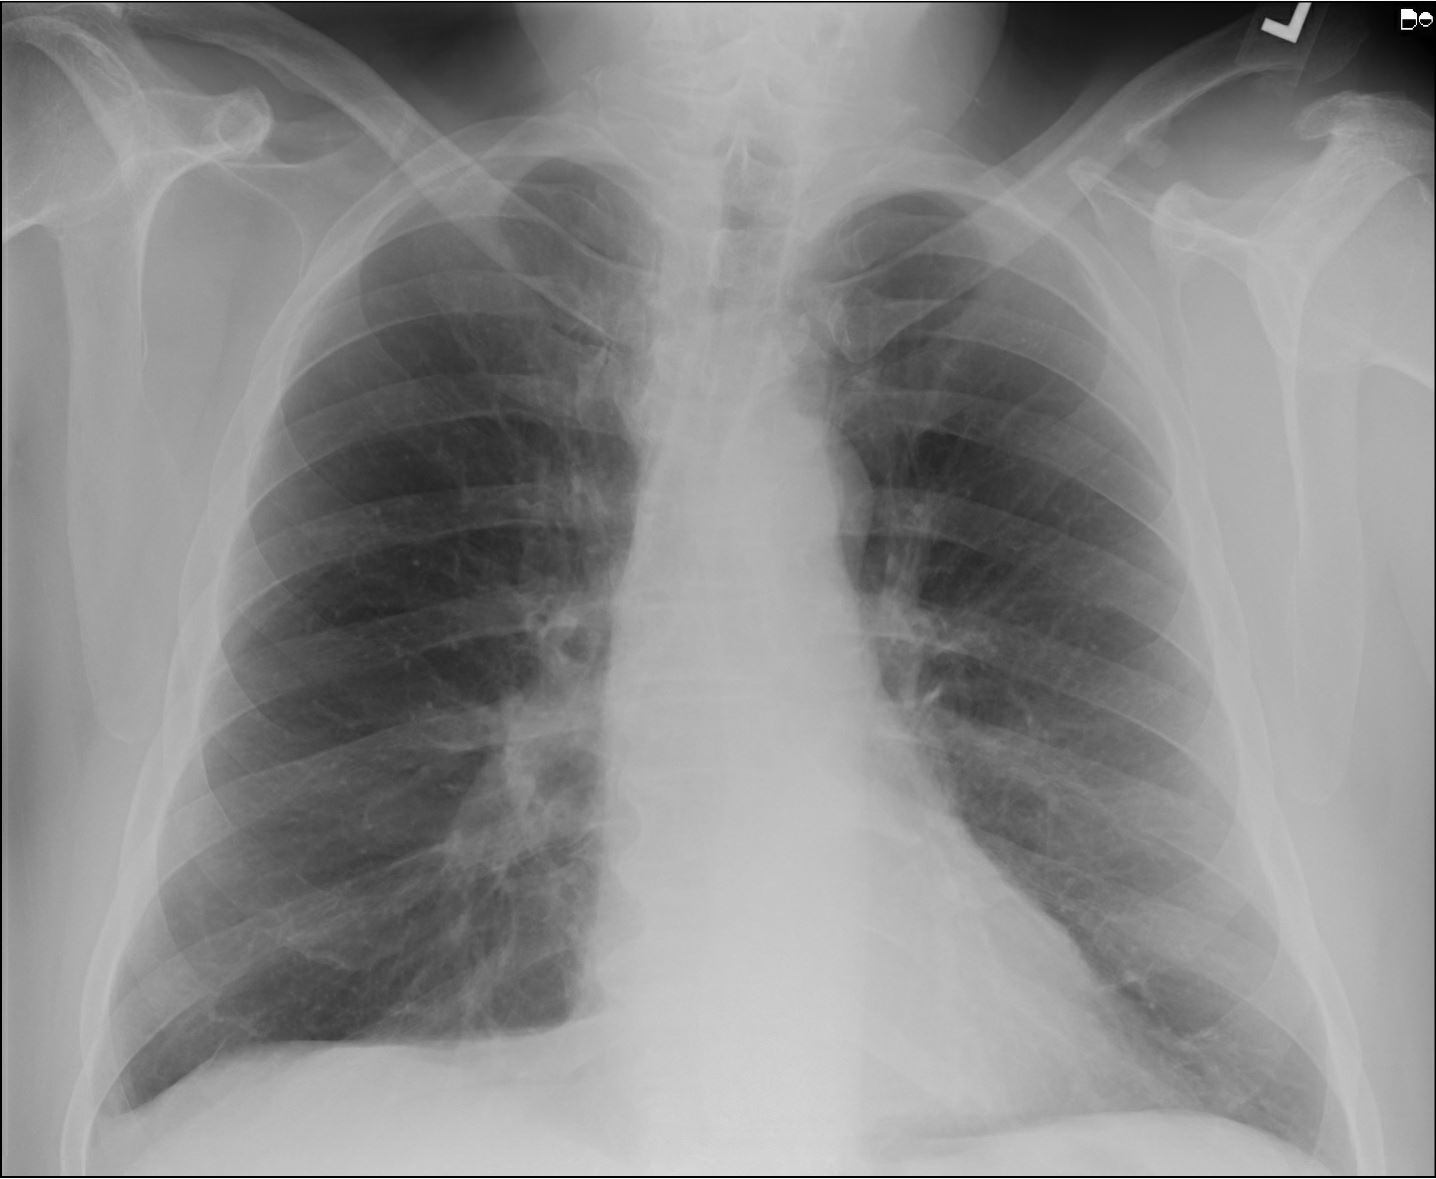

Normal chest xray 18 months post repair. Download Scientific Diagram